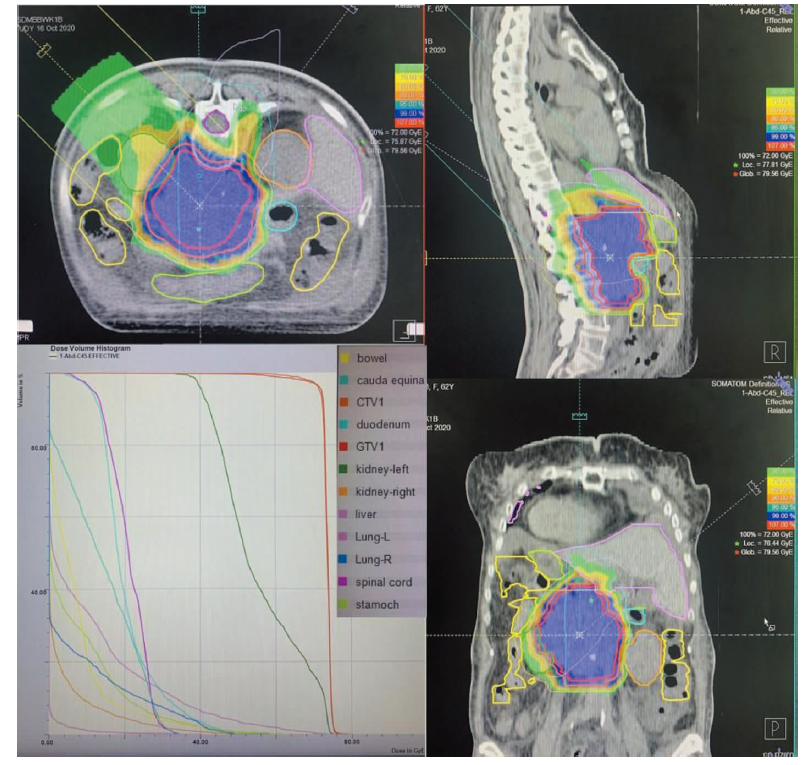

王征, 包慈航, 蒋国梁. 质子重离子放射治疗在腹膜后肉瘤治疗中的价值[J]. 外科理论与实践, 2022, 27(06): 506-510.

WANG Zheng, BAO Cihang, JIANG Guoliang. Value of proton and heavy ion radiotherapy in treatment of retroperitoneal sarcoma[J]. Journal of Surgery Concepts & Practice, 2022, 27(06): 506-510.